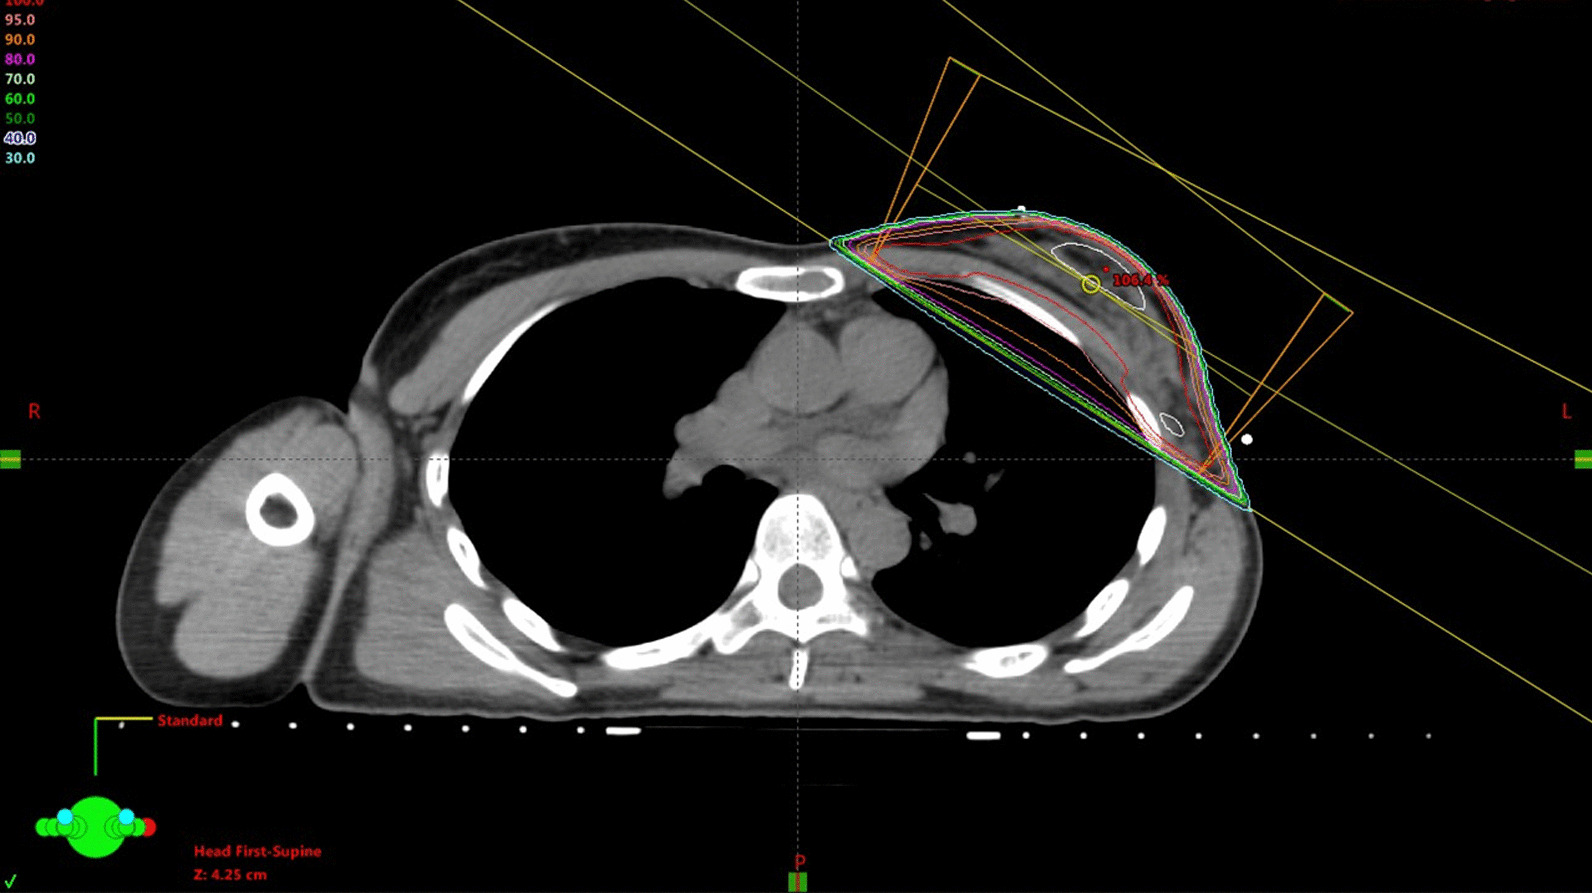

Fig. 1.

Dose distribution of radiation therapy. The left breast after partial mastectomy was treated with 50 Gy

One year before presentation to our hospital, a 40-year-old Japanese female presented to another hospital with lumpiness in her left breast. The patient had no medical history or family history of breast or ovary cancer. There was no history of drinking or smoking. At the previous hospital, a core needle biopsy revealed invasive ductal carcinoma, estrogen receptor-positive, progesterone receptor-positive, and human epidermal growth factor receptor 2-negative with a Ki-67 index of 23%. On the basis of the examination results, the patient was diagnosed with early breast cancer (cT1N0M0, cStage I) and underwent partial mastectomy with axillary lymph node dissection. After the mastectomy, the patient received radiation therapy (RT) with 50 Gray (Gy) in 25 fractions as initial irradiation for the left breast. After the initial irradiation of 50 Gy, she received 10 Gy in five fractions of a sequential boost for the tumor bed to a total dose of 60 Gy (Fig. 1). Tamoxifen was administered after RT.